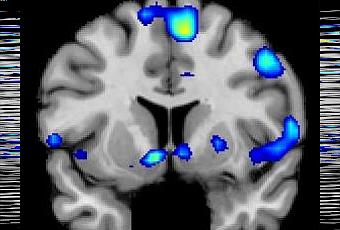

· ces pics de spiritualité sont associés et de façon reproductible à l’activation du noyau accumbens, une zone du cerveau impliquée fortement dans le traitement de la récompense.

· Ce pic d’activité cérébrale localisée intervient juste 1 à 3 secondes avant que les participants aient appuyé sur le bouton et cette observation est renouvelée à l’identique au cours de toutes les tâches de l’expérience.

ØEn plus des circuits de récompense du cerveau, les chercheurs constatent que les sentiments spirituels sont associés à l’activation de sites du cortex préfrontal médial, une zone du cerveau impliquée dans l’évaluation, le jugement et le raisonnement moral. D’autres zones associées à la concentration sont également actives.